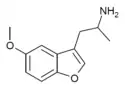

List of substituted α-alkyltryptamines

α-Alkyltryptamines are a group of substituted tryptamines which possess an alkyl group, such as a methyl or ethyl group, attached at the alpha carbon, and in most cases no substitution on the amine nitrogen.[17][18][19] α-Alkylation of tryptamine makes it much more metabolically stable and resistant to degradation by monoamine oxidase, resulting in increased potency and greatly lengthened half-life.[19] This is analogous to α-methylation of phenethylamine into amphetamine.[19]

5-MeO-αMT | 1-(5-methoxy-1H-indol-3-yl)propan-2-amine | 1137-04-8 |

Mebfap | 3-(2-aminopropyl)-5-methoxybenzofuran | 140853-59-4 |